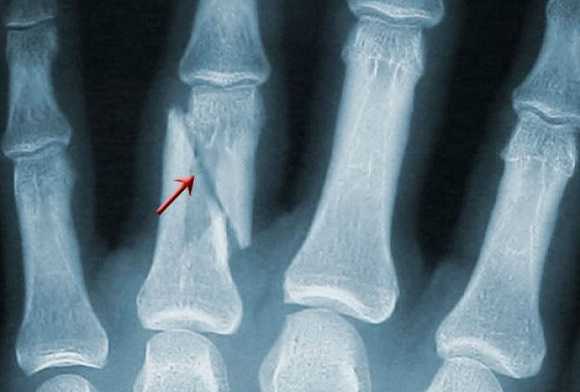

Травматические повреждения, такие как переломы, вывихи, трещины, смещения, - это первое, что можно обнаружить на рентгене лучезапястного сустава. Кости запястья, рентген которых показал перелом, имеют на снимке тёмные полосы различной локализации, размера и направления.

В структуре кисти - довольно много мелкоразмерных костей. Потому и видов переломов кисти существует тоже много:

- диафизарный (линия перелома располагается на теле кости), околосуставной (линия перелома - между концом кости и ее телом) и внесуставной (линия надлома - на конце кости);

- первичный (появляется при первичном травмировании в момент воздействия силы) и вторичный (смещение случается позже, в результате воздействия прикрепленных к сломанным костям мышц);

- стабильный (отломки остаются на прежнем месте) и нестабильный (случается вторичное смещение отломков).